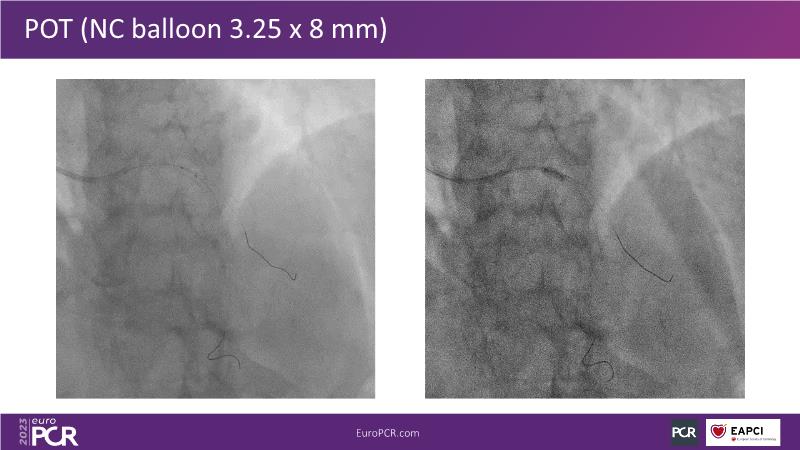

Join this session to explore the advantages of a fully optical approach in optimizing percutaneous coronary intervention (PCI) with the OptoWire III physiology wire and Nipro HF-OCT catheter. Through a practical case, you'll discover the significance of coronary physiology and intravascular imaging in bifurcation PCI and gain insights into how the performance and accuracy of the OptoWire III physiology wire can facilitate fast and reliable decision-making, particularly in side branch jailing scenarios.

- To review, through a practical case, the value of coronary physiology and intravascular imaging in bifurcation PCI